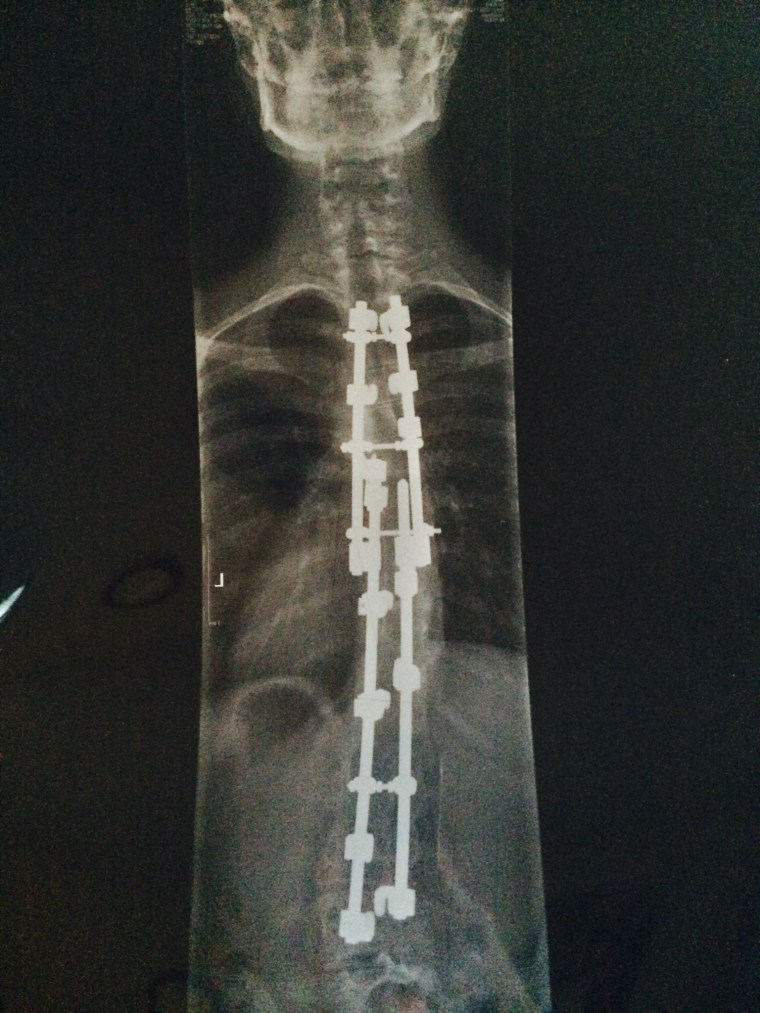

First let’s touch base about this picture:

This is my back and what it looks like currently…well 5 years ago when I had this X-Ray taken. I have 4 Harrington rods secured to my spine that will stay there forever. I had two scoliosis surgeries, one when I was 9 years old and the other when I was 10. My spine was not only curved but it was twisting my rib cage. Some, when diagnosed with scoliosis, have the option to wear a brace first to try and straighten out the spine. My only option was to have a pretty serious 14 hour surgery where my amazing surgeon would place two rods on both sides of my spine (lower back) . A year later at my check up I was told I needed to have my second surgery because my upper back was still curved. So I had another lengthy surgery to add two more rods from the middle of my back up to my neck.

I recovered well and have had some minor back pain throughout the years as my only “complication”. To be honest, I am blessed everything went as well as it did and I don’t take any of it for granted.